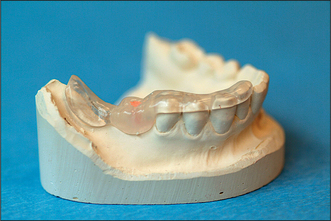

Special investigations

image

Fig. 11.19 An acrylic stent is placed in the mouth before radiography to evaluate the quality and quantity of bone at the desired site of implant insertion. Gutta percha inserted into a bur hole cut into the acrylic stent will assist in radiographic planning. The dimensions of the gutta percha and the angulation of the bur hole permit accurate assessment of the proposed implant site.

Most X-ray units do not give 1:1 magnification of the image: this must be borne in mind when planning the optimum dimensions of an implant from the radiographs. An acrylic stent may be used to determine the planned location of an implant. The stent is fitted over the teeth or edentulous jaw (Fig. 11.19) when the radiograph is taken.